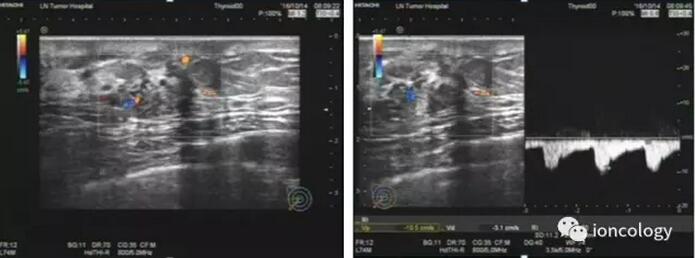

超声示:右侧乳腺外上象限见大小约13.0 mm×14.6 mm×11.7 mm不均质回声区,BI-RADS 4C级,局部可见强光点,内见丰富血流信号,测其中一条动脉,RI=0.70。